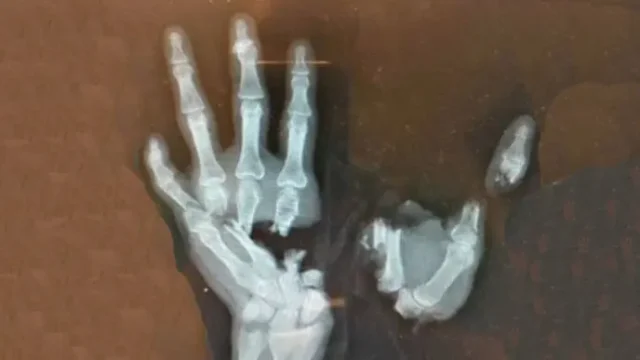

Na fotografiji je rentgenski snimak šake dečaka (12) koji je teško povređen prilikom eksplozije petarde u ruci. Eksplozija u njegovoj ruci uništila je šaku, a lekarima nije preostalo ništa drugo osim hitne amputacije. Rentgenski snimci, koje je porodica podelila s javnošću, otkrivaju svu ozbiljnost povrede i postali su upozorenje koje niko ne bi smeo da ignoriše, piše Magazinpolitika.rs.

Trenutak neopreznosti najčešće rezultira ozbiljnim povredama kostiju i tkiva, koje zahtevaju složene hirurške intervencije, dugotrajan oporavak i rezultiraju trajnom invalidnošću.